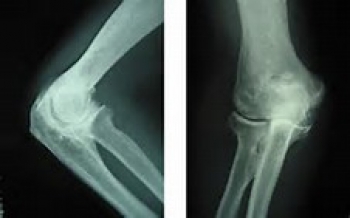

問診(職業の他、運動の経験などの問診)、診察、X線検査などを行います。

X線撮影で骨の変形具合を確認します。